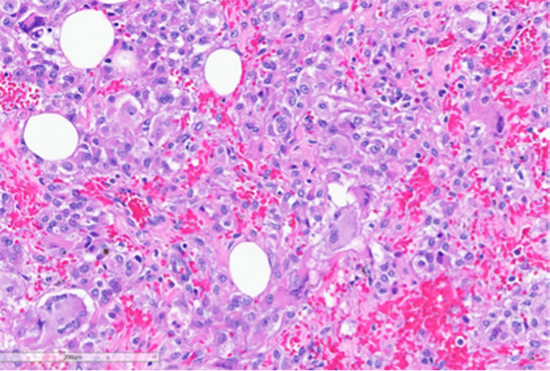

Figure 6: Foci of tumor with intermediate grade nuclear atypia with occasional multinucleated tumor giant cells (bottom left, black arrow) and bizarre cells with hyperchromatic nuclei (green arrows). (Hematoxylin and Eosin stained (20x)